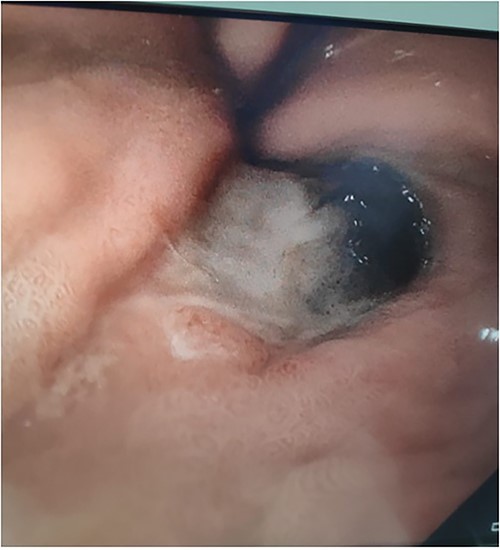

A 71-year-old female presented to a rural hospital with generalised abdominal pain and fevers in the context of a fall 3 days prior on a background of a myeloproliferative disorder, type 2 diabetes mellitis, cerebrovascular accident (CVA), chronic kidney disease and hypertension. The patient was tachycardic, febrile and had a peritonitic abdomen on examination. A computed tomography (CT) scan demonstrated a subcapsular splenic haematoma and haemoperitoneum. Urgent laparotomy revealed a sub-phrenic abscess and infected splenic haematoma for which uncomplicated splenectomy was performed. The postoperative course was initially uncomplicated with the patient tolerating diet, opening bowels and mobilising appropriately. Day 3 postoperatively, the patient developed burning central chest pain for which cardiac investigations were unremarkable. The patient received two units of packed red blood cells for a haemoglobin of 82 and intravenous proton pump inhibitor. The patient subsequently had a 250-ml episode of haematemesis and became haemodynamically unstable. Urgent upper gastrointestinal endoscopy demonstrated oesophageal necrosis from 20 cm from the teeth to the proximal margin of the gastro-oesophageal junction, diffuse bleeding from the distal oesophagus and adherent clot at the gastric fundus. The patient was transferred to a tertiary centre where repeat endoscopy demonstrated oesophageal necrosis and a well-circumscribed area of gastric fundus necrosis (see Figs 1–3) at the site of the adherent clot. Oesophageal biopsy demonstrated herpes simplex virus (HSV) 1-associated oesophagitis. Post-endoscopy the patient developed renal failure and failed extubation in intensive care. Given the multiple comorbidities of the patient and declining functional status prior to admission the family felt further invasive measures would not be in her best wishes. The patient was transitioned to comfort care and passed away the following day.

Upper gastrointestinal endoscopy image demonstrating gastric fundus necrosis.